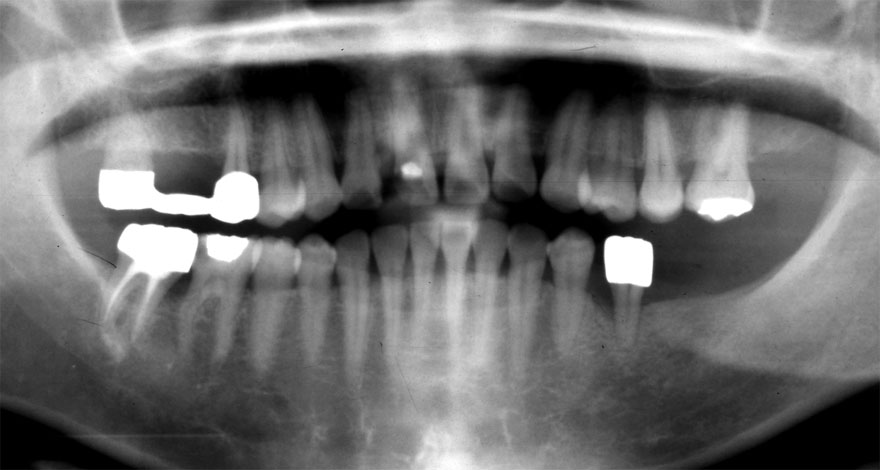

初診時 39歳 女性 平均歯槽骨喪失量:1.82mm

29年後 68歳

平均歯槽骨喪失量:2.21mm

29年間喪失量:-0.39mm

年間喪失速度:-0.013mm

(ケア頻度:5.55ヵ月ごと)